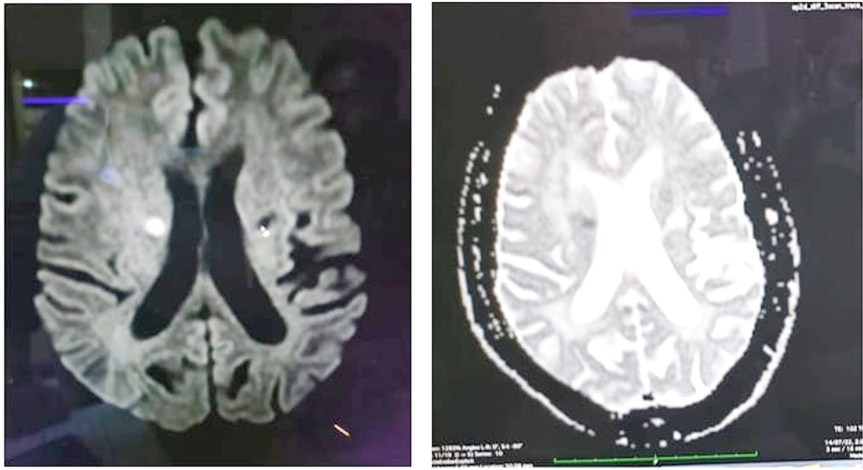

Background: Emotional lability is described as stereotypical affective outbursts which is not reflective of internal emotion. We present a case of caudate nucleus infarct presented as pathological crying.

Case Description: A 56-year-old man presented with abrupt onset history of pervasive episodes of crying since a week. His brain imaging had shown an acute infarct in right caudate nucleus.

Conclusion: Our patient had episodes of pathological crying due to disruption in subcortical thalamic-ponto cerebellar network. It is important to note that physicians and psychiatrist should be aware of unusual manifestation of right caudate nucleus infarct as pathological crying.